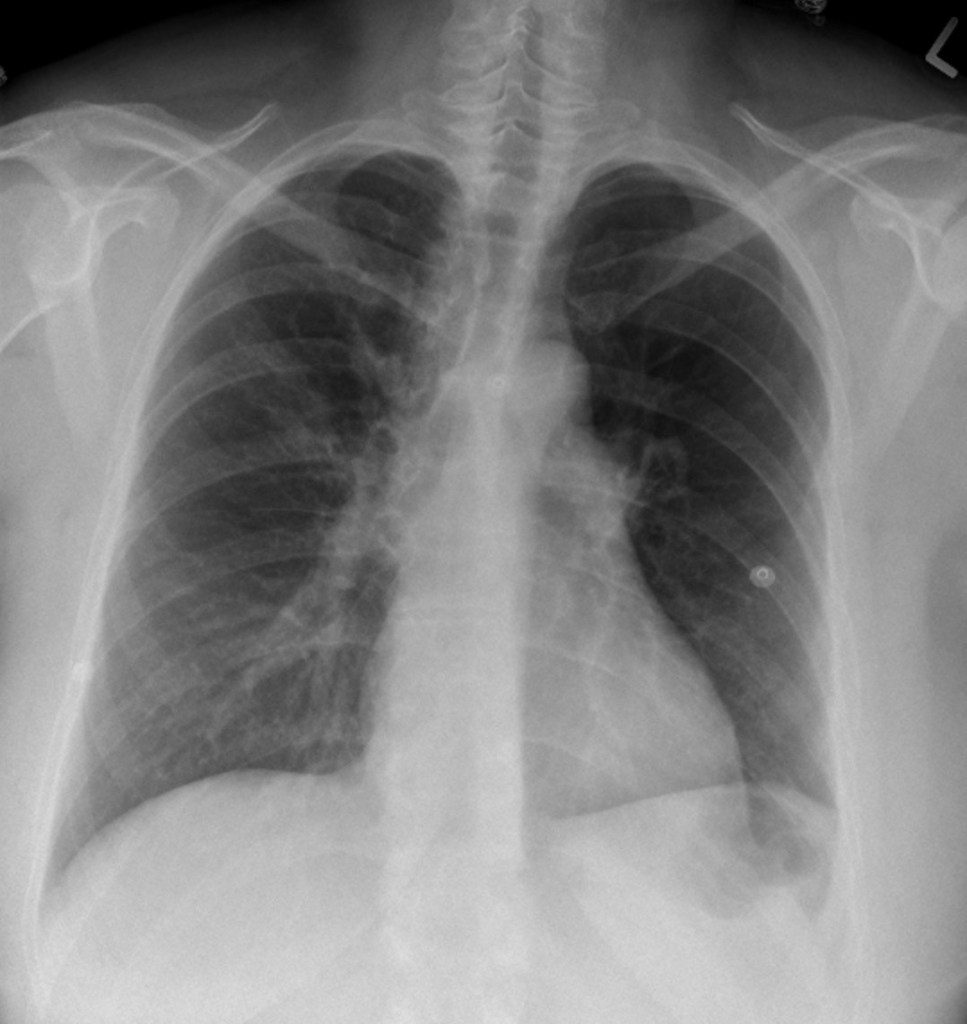

Chest X-ray for the Case

This case involves the approach to the patient with acute dyspnea. The patient is tachypneic but with an otherwise normal respiratory exam. ECG shows new right heart strain. The team should consider multiple possibilities but recognize PE as the most likely cause.